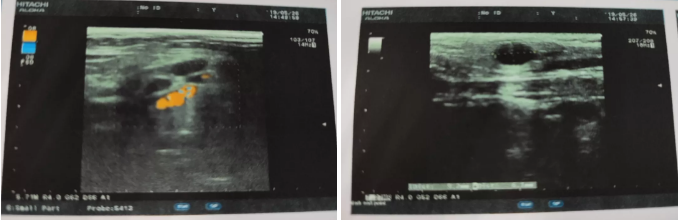

患者超聲檢查報告